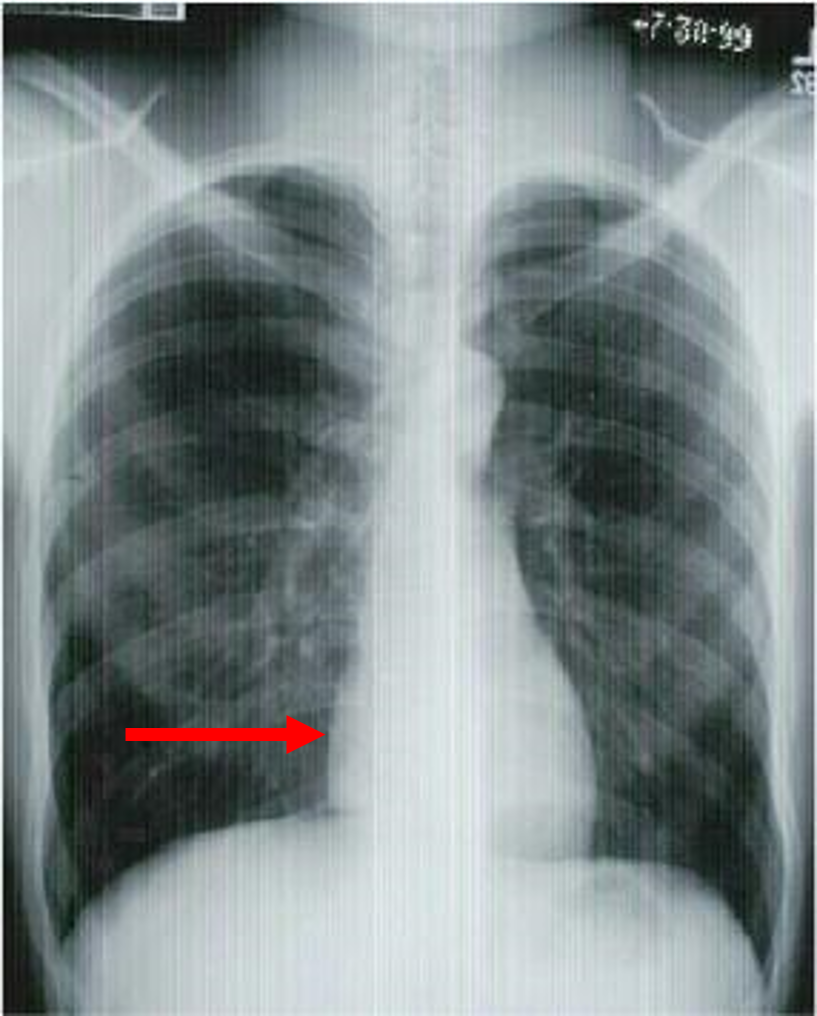

what view is this?

give three indicators

PA chest

aortic arch

diaphragm

left ventricle

liver

pulmonary artery

right atrium

right mainstem bronchus

stomach

trachea